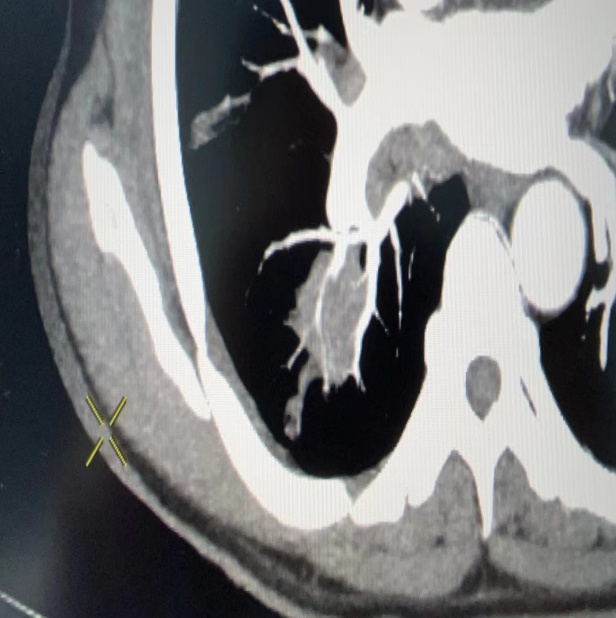

另一例患者,男性,80岁,院外发现右肺部占位,慕名前来就诊,家属希望明确肺部占位性质,PET-CT诊断肺部占位,前列腺占位,肋骨、骨盆多发骨质代谢增高。支气管镜检查,发现病变受累支气管开口呈缝隙样狭窄,活检钳无法进入,取到病变部位组织。医院组织多学科(MDT)会诊,专家认为,患者及家属拒绝化疗、放疗及手术治疗,同意微创及靶向治疗,明确诊断是家属第一诉求,建议CT引导下经皮肺穿刺活检射频消融术。考虑患者高龄,基础病多,病变内部及周围遍布较粗血管,穿刺出血风险极高。张德信教授详细阅片后,考虑消融正常范围应距病变边缘5mm-10mm,才能保证肿瘤完全消融,但标准范围的消融必将损伤周边大血管,导致致命性大咯血,遂建议先活检,明确诊断后再决定进一步治疗。张德信教授亲自和患者家属谈话,告知此次穿刺操作的目的、方式、风险、预后等。张德信教授认真阅片后,2次穿刺均成功避开血管,取材成功,患者无咯血,手术过程顺利。